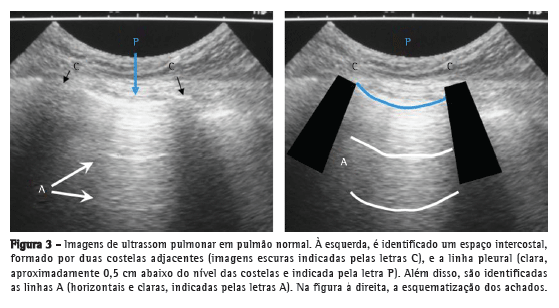

Inicialmente, com o aparelho de ultrassom no modo B, posiciona-se o transdutor com seu marcador direcionado para a cabeça do paciente e perpendicular às costelas, obtendo-se a imagem típica do USP.(4,6) Os espaços intercostais adjacentes são examinados deslizando-se o transdutor verticalmente (Figura 3).(10)

As costelas bloqueiam as ondas do ultrassom e são identificadas por sua sombra acústica posterior (letra C na Figura 3), que impede a visualização das estruturas mais profundas. Aproximadamente 0,5 cm abaixo delas, uma linha horizontal clara (hiperecogênica) é visualizada, chamada linha pleural (letra P na Figura 3). Essa linha resulta do encontro da pleura visceral com a parietal, e sua cintilância se deve ao deslizamento entre elas (deslocamento do ar).

O parênquima pulmonar normal (assim como qualquer estrutura anatômica preenchida por gases) não é visível além da pleura, pois a presença de ar impede a propagação da onda do ultrassom. Esse fato gera um artefato de repetição, que é identificado no exame como a presença de linhas horizontais claras (hiperecogênicas), sem movimento, que se repetem em intervalos iguais, chamadas de linhas A (letra A na Figura 3).